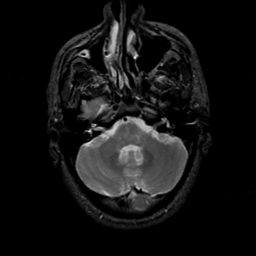

MR Study #22, December 1, 1991 -- Slice #11